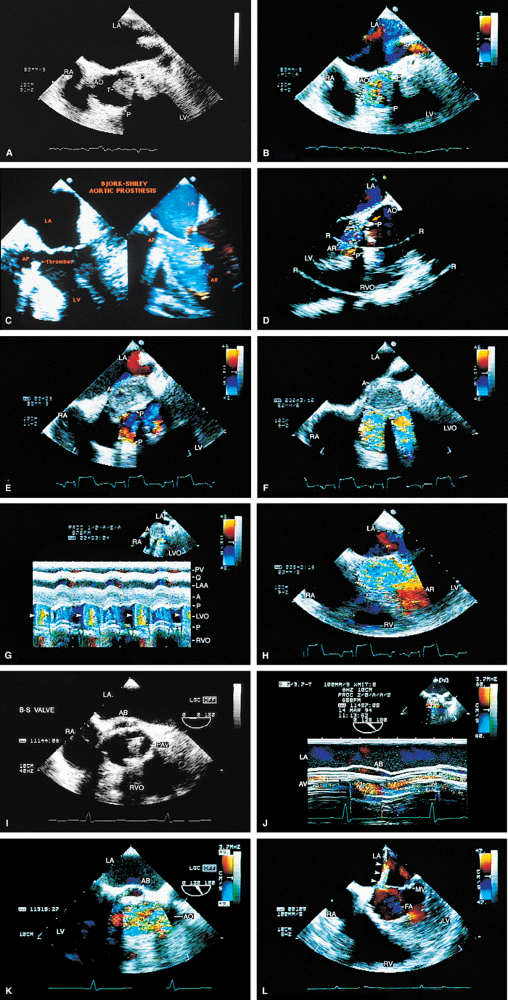

FIGURE 5.19. Porcine mitral prosthesis: stenosis and regurgitation. A. A large diastolic flow acceleration (arrowheads) on the atrial side of the prosthesis (P), suggesting the presence of obstruction. B. Thickening and calcification of the prosthesis resulting from degeneration. C. A decreased slope of the diastolic velocity profile with a measured mitral valve area (MVA) of 0.9 cm2 measured by the pressure half-time technique, indicating significant obstruction. D. Associated severe valvular mitral regurgitation (MR) (arrowheads). Images B through D are from the same patient. AO, aorta; LA, left atrium; LV, left ventricle; PA, pulmonary artery; RA, right atrium; RV, right ventricle; RVO, right ventricular outflow tract. |

FIGURE 5.20. Porcine mitral prosthesis: spontaneous contrast and thrombus in the left atrium (LA). A. M-mode study shows spontaneous contrast (arrows). B,C. A large thrombus (TH) in the left atrial appendage (LAA). The prosthetic leaflets are only mildly thickened (B). D. Extensive thrombus formation (TH) in the left atrium in another patient with an obstructed porcine mitral prosthesis. AO, aorta; LV, left ventricle; MVP, mitral valve prosthesis; RA, right atrium; RVO, right ventricular outflow tract. (Creproduced with permission from Mahan EF III, Nanda NC. Transesophageal echocardiography. In: Rackley CE, ed. Challenges in Cardiology I. Mt. Kisco, NY: Futura, 1991:85–101. ) |

FIGURE 5.21. Porcine mitral prosthesis: paravalvular regurgitation. A. A laterally located area of prosthetic (MP) dehiscence (arrow). B–D. An eccentric jet of mitral regurgitation (MR) (arrowheads) originating in the area of prosthetic (P) dehiscence. E. Color M-mode demonstrates systolic backflow (arrows) in the left upper pulmonary vein (LUPV), indicative of severe MR. After repair, the dehisced area is no longer seen (F), and there is absence of systolic backflow in LUPV (G). AS, atrial septum; FA, flow acceleration; LA, left atrium; LV, left ventricle; RA, right atrium; RV, right ventricle. |

FIGURE 5.22. Porcine mitral prosthesis: paravalvular and valvular regurgitation. A. Thickened prosthetic (P) leaflets (arrowhead) and a large area of lateral dehiscence (arrow). B. Valvular and paravalvular mitral regurgitation (MR) (arrowheads). C. Prominent systolic backflow (arrows) is noted in the left upper pulmonary vein (LUPV). D–F.Another patient with thickened prosthetic (MVR) leaflets, prominent diastolic flow acceleration, and lateral paravalvular regurgitation (arrows). The MR jet is narrow as a result of the Coanda effect, caused by the jet impinging against the left atrium (LA) lateral wall. Systolic backflow was present in the LUPV, however, indicative of severe MR. This was confirmed by angiography. LV, left ventricle; RVO, right ventricular outflow tract; RA, right atrium. |

FIGURE 5.23. Mitral prosthesis: valvular regurgitation. A–C. S represents the valve stents, and the arrow in B points to a suture. Color Doppler examination demonstrates three jets of mitral regurgitation (MR) (E) associated with two areas (arrows) of prominent flow acceleration on the ventricular side of the prosthesis in D. F. Systolic backflow in left atrial appendage (LAA) indicates severe MR. Although MR was pansystolic in this patient, the systolic backflow occurred only in mid- and late systole, because it takes some time for the MR jet to travel to LAA from the prosthesis. G. Postoperative study shows absence of severe MR and two jets (arrows) of mild, normal mitral prosthetic (MP) regurgitation. LA, left atrium; LUPV, left upper pulmonary vein; LV, left ventricle. |

FIGURE 5.24. Porcine mitral prosthesis: degeneration. A. Heavily calcified mitral prosthetic (MP) leaflets (arrow). S, prosthetic stents (shown in A and B). C,D. The calcified leaflets (arrows) and the prosthetic ring (R) are viewed in short axis. LA, left atrium; LV, left ventricle; RV, right ventricle. |

FIGURE 5.25. Porcine mitral prosthesis: cusp rupture. A. Marked bowing (arrow) of the prosthetic (P) leaflets into the left atrium caused by prolapse. There is no evidence of cusp rupture. B–F. Rupture of the cusps (arrowheads) is seen. Note prominent linear protrusion of the ruptured leaflets into the left atrium (LA). F. Coarse systolic flutter of a ruptured cusp (arrowhead). G. Torrential mitral regurgitation (MR), together with a large area of flow acceleration (FA), on the ventricular aspect of the prosthesis. B and C are from one patient; D–G are from another patient. H,I. Another patient with porcine cusp prolapse and rupture (arrowhead in H), with severe MR (arrowheads) and prominent FA in I. J–L. Rupture of thickened porcine mitral cusps (arrowheads in J,K) with severe, eccentric MR (arrowheads in L) through the prosthesis (P). M. Another patient with porcine (P) cusp rupture with severe MR (arrows) shown in both color two-dimensional and M-mode images (arrows). N. The arrow points to severe valvular MR from cusp rupture; arrowheads show associated severe paravalvular MR. O,P. Gross specimens show porcine prosthetic cusp rupture. LA, left atrium; RA, right atrium; LV, left ventricle; RV, right ventricle; LVOT, left ventricular outflow tract; RVO, right ventricular outflow tract. |